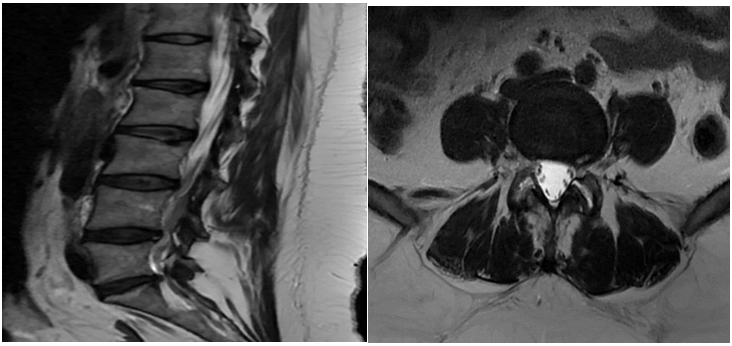

Journal-Neurological-Disorders-Patient

Figure 5. CT cervical spine for the same patient shows Straightened cervical curve. Mild spondylodegenerative changes at C5-C6 and C6-C7 levels. C6-C7 posterior and right posterolateral disc herniation, with a traction osteophyte.

Journal-Neurological-Disorders-One

Figure 6. MRI of the cervical spine after one year shows a slight interval size reduction of previously identified large right paracentral disc extrusion at C6-7. Persistent right paracentral large disc osteophytic complex of the exiting right neural foramen.